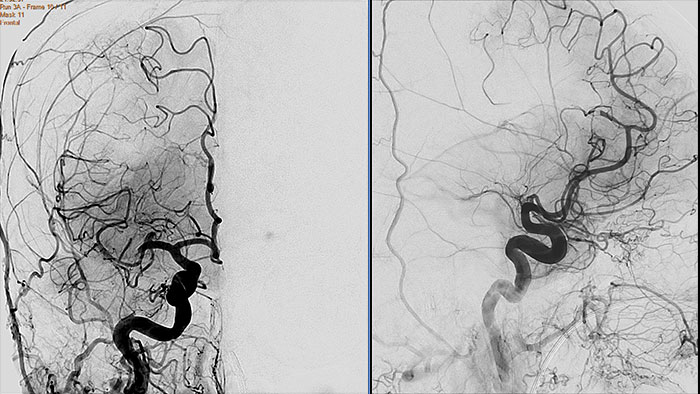

Contrast arterial structures with surrounding bone and soft tissue to assist in identification of vascular abnormalities

The XA Vascular Processing – DSA (in MMV) expands your workflow by allowing you to read and post-process iXR images virtually anywhere. Obtain images of arteries in various parts of the body using tools to perform standard and run subtractions, pixel shifting, and landmarking. This application also provides post-processing tools to edit and optimize the DSA XA data created in the interventional room.